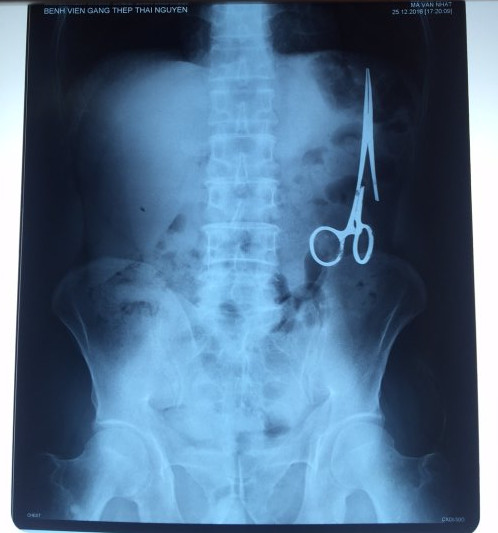

遺留在病人腹中的剪刀

據(jù)越南青年報(bào)1月2日報(bào)道,在越南首都河內(nèi)醫(yī)療專家的幫助下,越南東北部的太原?。═hai Nguyen)鑄鋼醫(yī)院的醫(yī)生日前從54歲患者M(jìn).V.N腹中取出一把醫(yī)用剪刀。這把剪刀是此前曾為M.V.N手術(shù)的醫(yī)生遺留的,已經(jīng)在其腹中待了18年時(shí)間。

醫(yī)務(wù)人員表示,這把剪刀遺留在病人腹部左側(cè),與結(jié)腸緊挨著。剪刀的把手已經(jīng)生銹,部分器官也已經(jīng)與剪刀粘連起來。但在過去多年中,M.V.N沒有任何不適感覺,也從未因?yàn)榱粼诟怪械募舻兑l(fā)的相關(guān)問題去看過醫(yī)生。直到2016年12月,M.V.N因?yàn)樵庥隽艘粓鲕嚨?,才到鑄鋼醫(yī)院進(jìn)行身體檢查。

超聲波檢查顯示,M.V.N的腸子中有個(gè)奇怪物體,看起來就像醫(yī)用剪刀。M.V.N證實(shí),他曾于1998年6月份在北江省綜合醫(yī)院接受手術(shù),在此后也從未進(jìn)行過任何手術(shù)。近來,他感到腹部有些疼痛,并試圖通過服用藥物治療。12月27日,M.V.N回到北江省綜合醫(yī)院再次進(jìn)行超聲波檢查,顯示其腹部的確存在怪異物體。